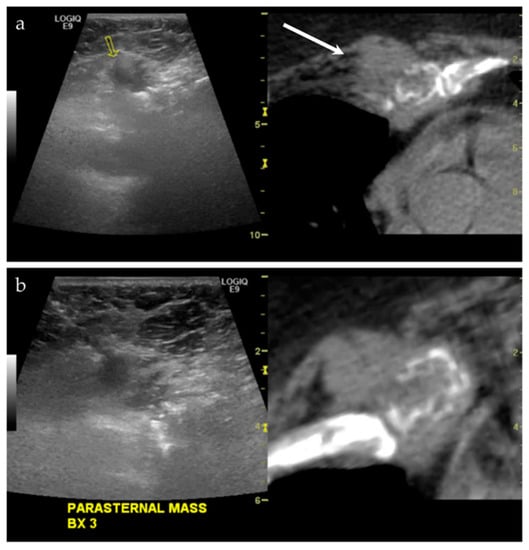

| NA/F | Right parasternal region | US-CT | Metastatic disease, lung adenocarcinoma | Neoplastic, malignant |